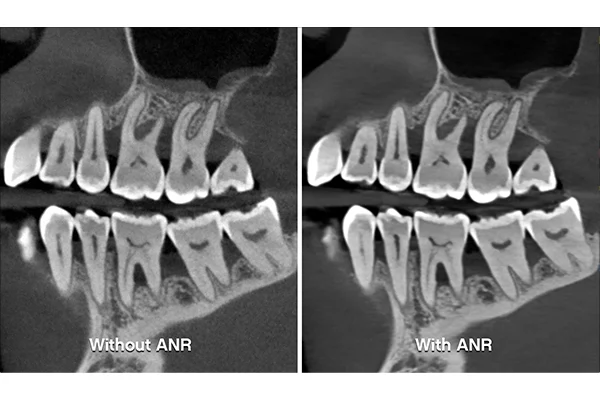

• ANR pokročilá redukce šumu